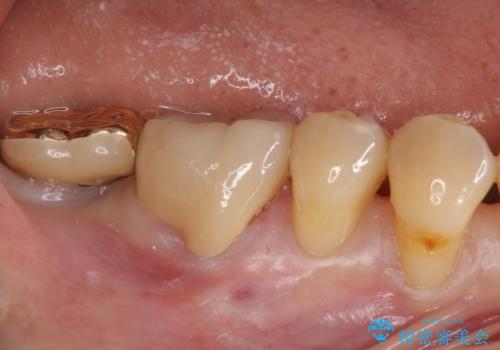

- 昔つめた材料が欠けたこと、歯の捻転を主訴に来院されました。

矯正治療の希望はなかったため、被せ物で歯の形を修正することになりました。

不適合だった詰め物の裏側に大きな虫歯がありました。

セラミックインレーやアンレーでは強度に不安が残るため、クラウンでの修復処置としました。

クラウンでは歯のがたつきを修正することもできます。

虫歯の除去と歯の捻転の両方を解決することができました。